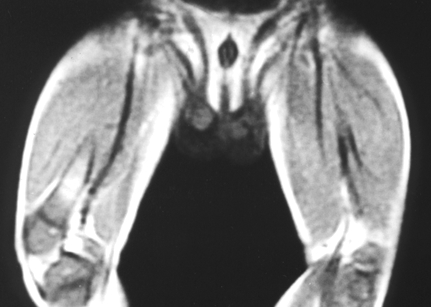

근육병(Myopathy)

관련질환

듀시엔형 근이영양증

베커형 근이영양증